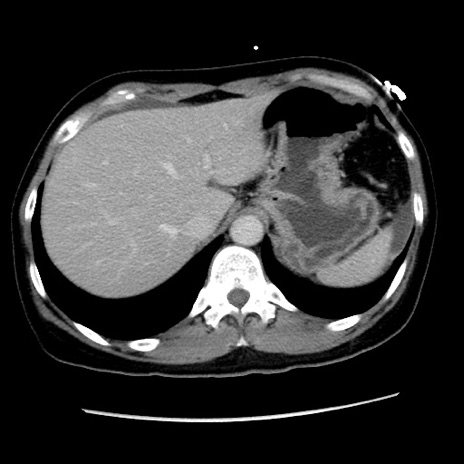

症例10(横断像)

【症例】 50歳代女性

【主訴】 腹痛

【現病歴】前日生レバーを食べた。今朝に排便あり。 昼前に突然発症の腹痛を生じ、当院救急外来を受診した。

【既往歴】 子宮筋腫にてで子宮全摘後

【身体所見】 意識清明、腹部:平坦、軟、下腹部やや左を中心に圧痛・反跳痛あり、筋性防御あり

【データ】WBC 7800、CRP 0.07